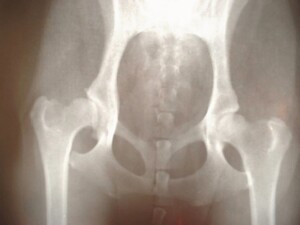

股関節は骨盤と大腿骨をつなぐ大きな関節で、立つ・歩く・座るなど日常の動作を支える重要な役割を担っています。人体で最も可動域が広く、体重を支え続けるため大きな負担がかかる部分でもあります。

1. 変形性股関節症

加齢や骨格のアンバランスにより、関節軟骨がすり減り炎症や変形が進行する疾患。特に女性に多く見られます。